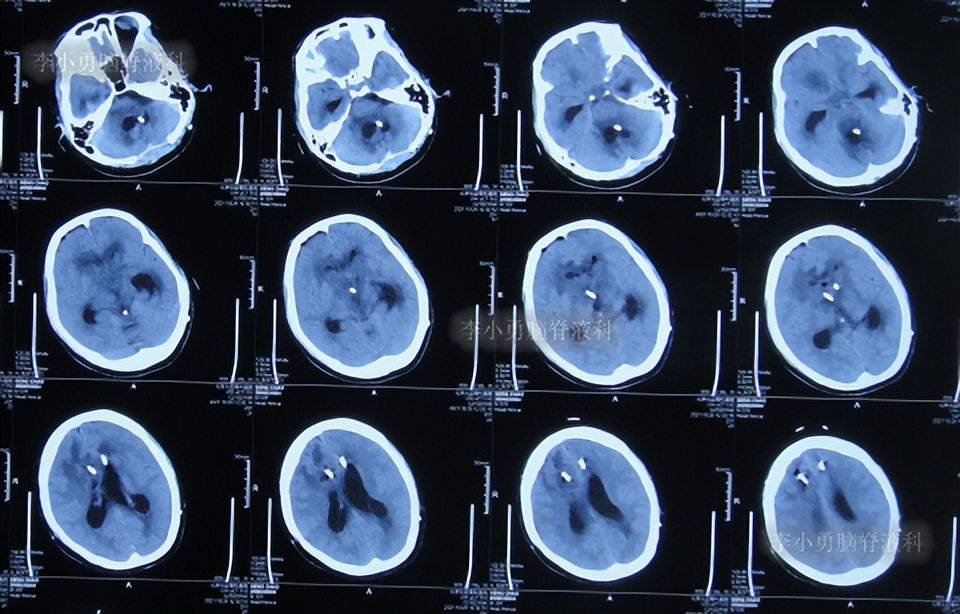

第4次出院后2个月时间内,期间曾4次查头颅影像均示脑室有进一步扩张(图-12、图-13、图-14、图-15),且患者精神逐渐变差。

图-12:2020年3月14日头颅CT

图-13:2020年3月31日头颅核磁

图-14:2020年4月18日头颅CT

图-15:2020年5月9日头颅核磁

第5次住院治疗

第4次出院后2个半月即2020年5月14日,患者意识变差,且不能下地活动,第5次就诊于给予手术的医院,查头颅CT示脑室扩张加重(图-16)。

图-16:2020年5月14日头颅CT